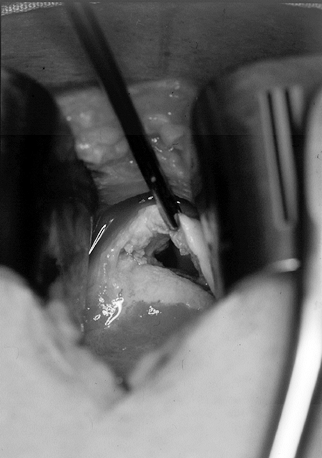

routine fashion. Arthroscopy is often helpful to identify the extent

and reparability of a tear (Fig. 79.11 and Fig. 79.12). If the tear appears reparable with or without mobilization of the cuff, proceed with arthroscopic repair. (See below for the management of irreparable tears.) After decompression, perform arthroscopic mobilization of the cuff if desired, or proceed with open surgery.

Figure 79.11.

Arthroscopic view of a full-thickness tear with an obvious acromial

spur overhead and an intact biceps tendon beneath a slightly retracted

tear of supraspinatus.

Figure 79.12. Incision parallel to the acromion to expose a rotator cuff tear. Arm is still suspended from overhead traction. -

With the patient in the same position, make a strap incision paralleling the lateral edge of the acromion (Fig. 79.12).